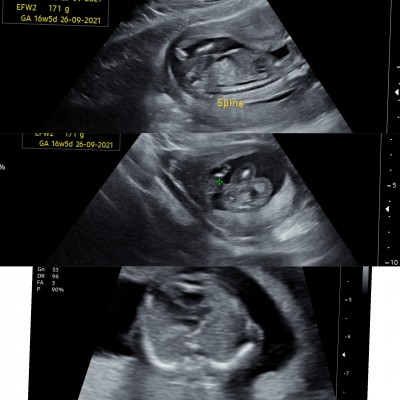

kızlar doktorum birsürü resim verdi ama hangisi bebegimin bacak arası ya anlayamadim

En alttaki. Popodon almış resmi bacaklar yukarıda. Sanırım kız öyle mi Allah bağışlasın

Sanırım en sonda ki bacak arası diğerleri uzuv ölçümleri cunki be cinsiyeyode kız gibi canım eger o bacak arasında ")

En üstte bacak arasında çıkıntı var kordon olabilir. En altta da bacak aradı boş. Büyük ihtimalle kız

16 haftalik belli olmalıydı aslında cinsiyeti.